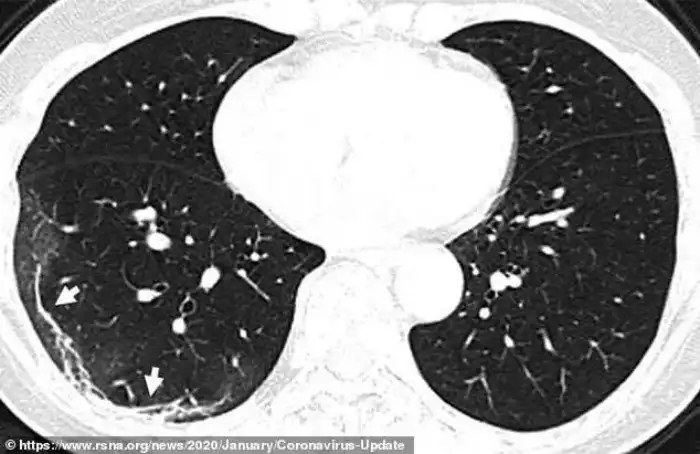

Это - снимок легких 45-летней женщины из Сычуани, протестированной после возвращения из Японии и диагностированной как носительница вируса. На снимке видно некоторое количество аналогичных образований, но здесь они сосредоточены в верхней доле левого легкого.